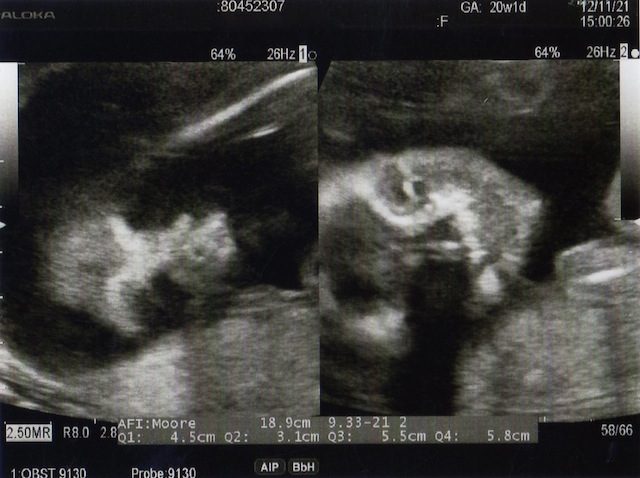

Nt エコー

23週 Nt 胎児頚部浮腫 について 妊娠後期 5ヶ月 6ヶ月 7ヶ月 8ヶ月 9ヶ月 ベビカム相談室 ベビカム

エコー画像 首のむくみ1 4 Nt 胎児頚部透過像 39歳で出産予定 10歳年上夫と不妊治療 By北国のマリー

Nt 胎児後頚部浮腫 首の後ろの浮腫 について 気ママんの妊娠 育児奮闘記 3人目3回目の帝王切開で出産しました

Nt

02 妊娠初期 胎児の頸部浮腫 Nt 妊娠11 13週でcheck 深谷産婦人科 医学情報

胎児の首の後ろのむくみ 浮腫 Nt とは 妊娠初期 All About

胎児の首の後ろのむくみ 浮腫 Nt とは 妊娠初期 All About

胎児の首の後ろのむくみ 浮腫 Nt とは 妊娠初期 All About

胎児の首のむくみ Nt クリフム夫律子マタニティクリニック

Nt 胎児頚部浮腫 のエコー画像 携帯ホームページ フォレスト